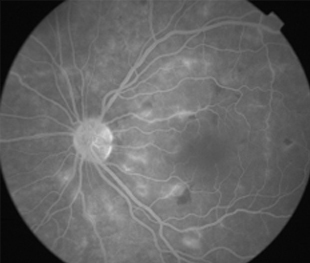

Angiografía OI

- Angiografía: teñido arterial, escape capilar, más tardíamente, no perfusion arteriolar y venular con teñido de las paredes vasculares y dilatación venosa.